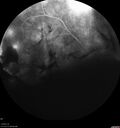

PDR and Vitreous hemorrhage - Second FA is following PRP laser257 views42 year old man (date 2018): Prior to 2 months ago the vision in the right eye was good. This started with a glob in the vision and then the vision got better. Then the string came back down and is getting bigger and bigger. The last time he had bleeding in the left eye he had surgery in 2009. The left eye is now doing OK other than there is a cataract. The right eye had some laser treatment done in 2009. The vitrectomy and laser were done at William Beaumont.

VA OD: sc3'/200 NscUnable

VA OS: sc20/40 NscJ2-1